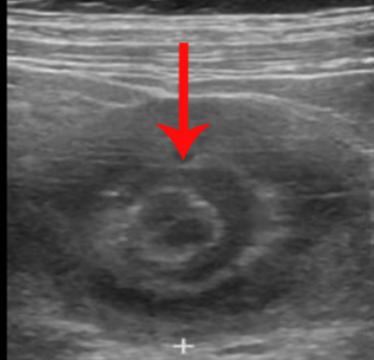

彩超和腹部CT对诊断肠套叠有较高的诊断率。肠套叠的腹部CT表现一般为软组织肿块影,常呈现"同心圆征"或"靶环征",有时称假肾征。有时肠管套入部较深,可表现为"双肠管征"。

彩超下的同心圆征